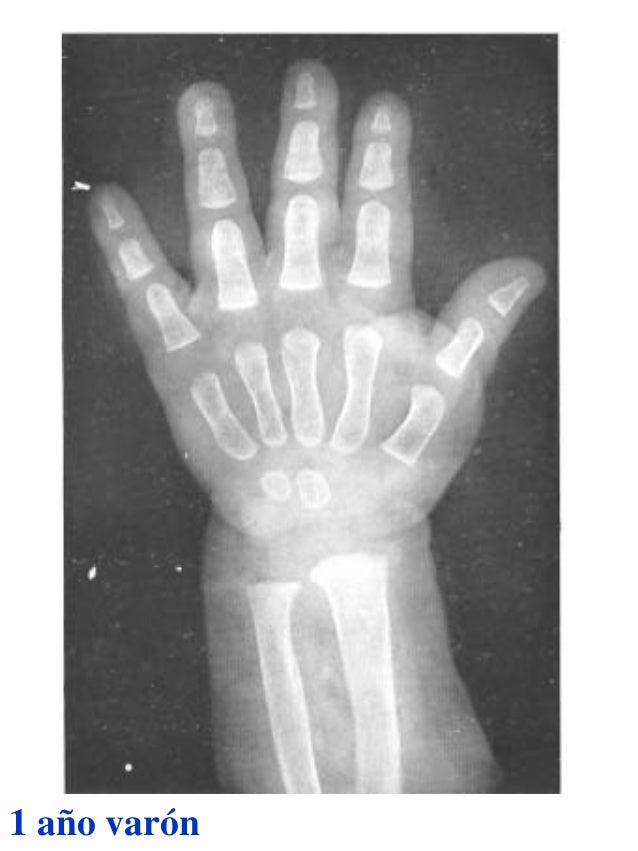

Figura 2 Imágenes de radiografías de mano y muñeca izquierda del

Figura 2 Imágenes de radiografías de mano y muñeca izquierda del Tablas De Greulich Y Pyle Edad Osea The greulich and pyle atlas is used to estimate the age of children and adolescents. El método de greulich y pyle(1) es un método simple de valoración de la edad ósea en pacientes pediátricos. El diagnóstico y la clasificación se basan en el examen físico, el análisis del crecimiento, la maduración ósea, la ecografía de útero y gónadas, y los. Tablas De Greulich Y Pyle Edad Osea.